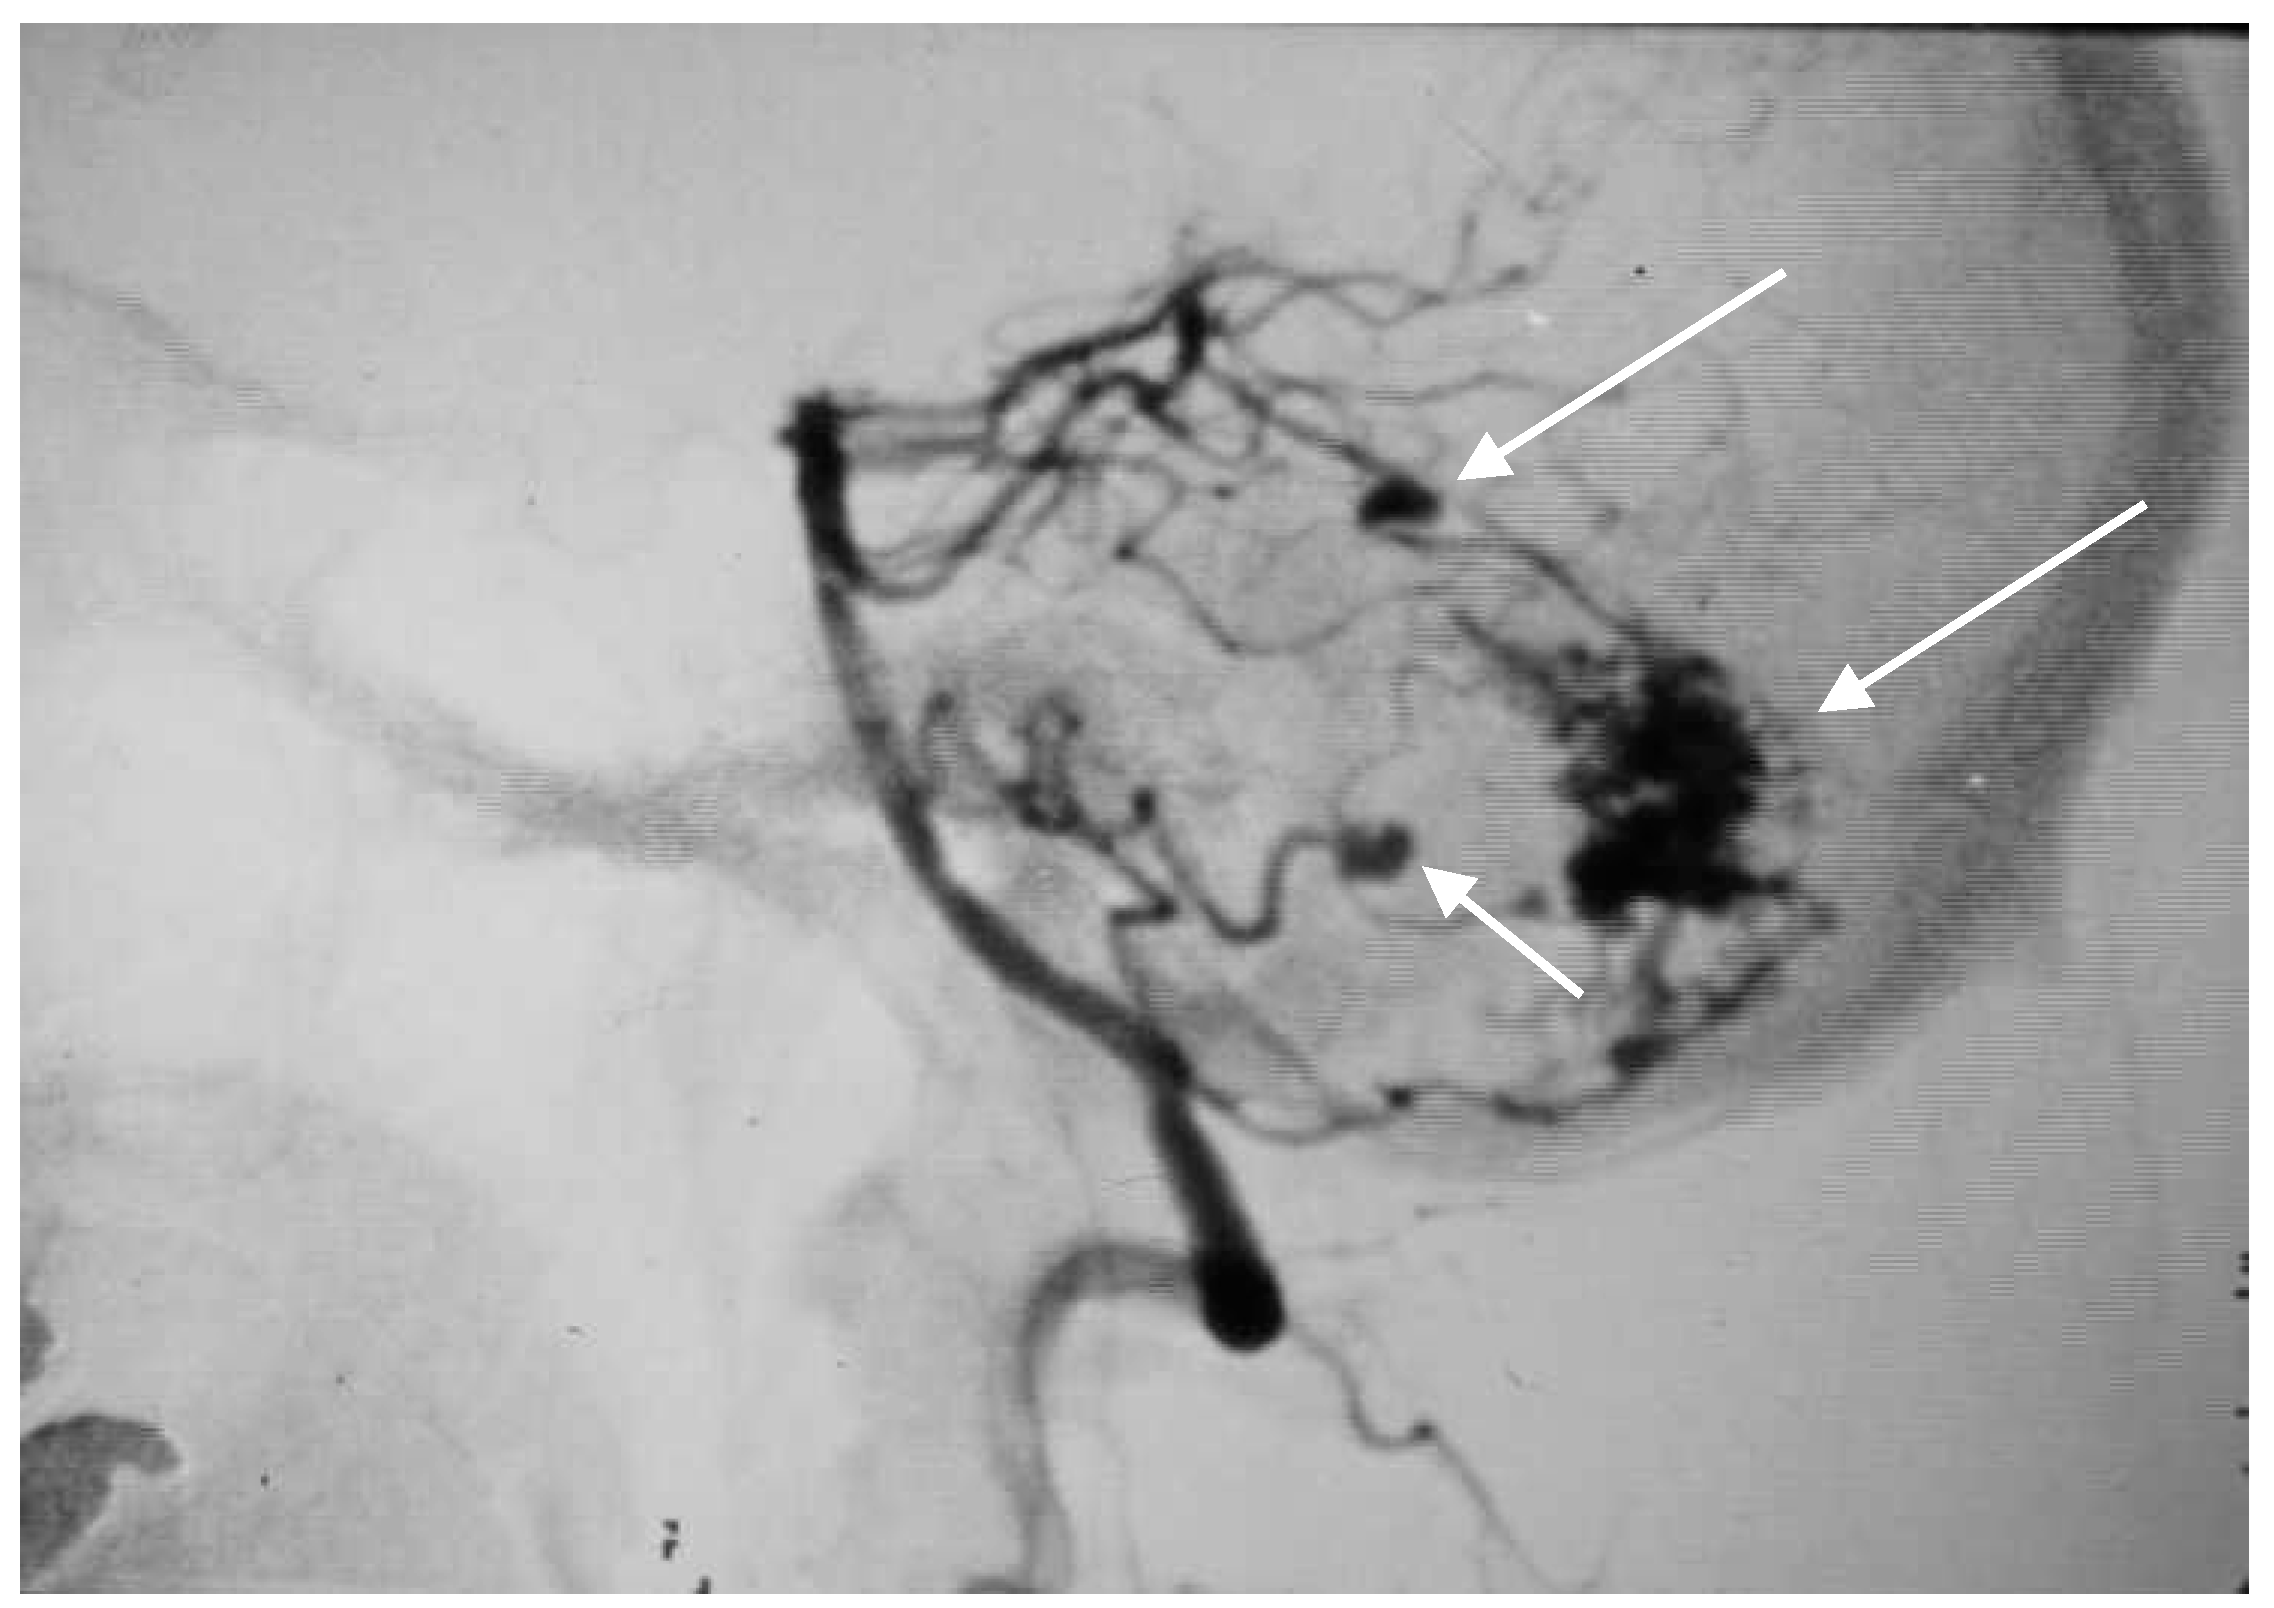

A 60-year-old woman was admitted for abrupt loss of consciousness. CT in a peripheral setting showed cerebellar hemorrhage with a pan-intraventricular hematoma in the fourth ventricle and a massive SAH in the cerebellar and spinal canal regions (Figure 4). AG revealed three aneurysms on the distal PICA (Figure 5), successfully excluded from circulation by microsurgery clipping while maintaining patency of the PICA. During the surgery, sudden intraoperative rupture occurred from the most peripheral aneurysm, located just under the arachnoid membrane on the surface of the cerebellum. After easy clipping of the neck, the feeding vessel was followed in the hematoma to its telovelotonsillar part, where another two aneurysms were visible. With the technique of temporary clipping, the optimal final position on both clips was achieved in the wide necked aneurysms. The patency was confirmed with intraoperative ultrasound. A difficult postoperative course and hydrocephalus required temporary ventricular drainage, which was converted to a ventriculo peritoneal (VP) shunt with a good long-term result.

Figure 5. Oblique projection of an angiogram with three PICA aneurysms.